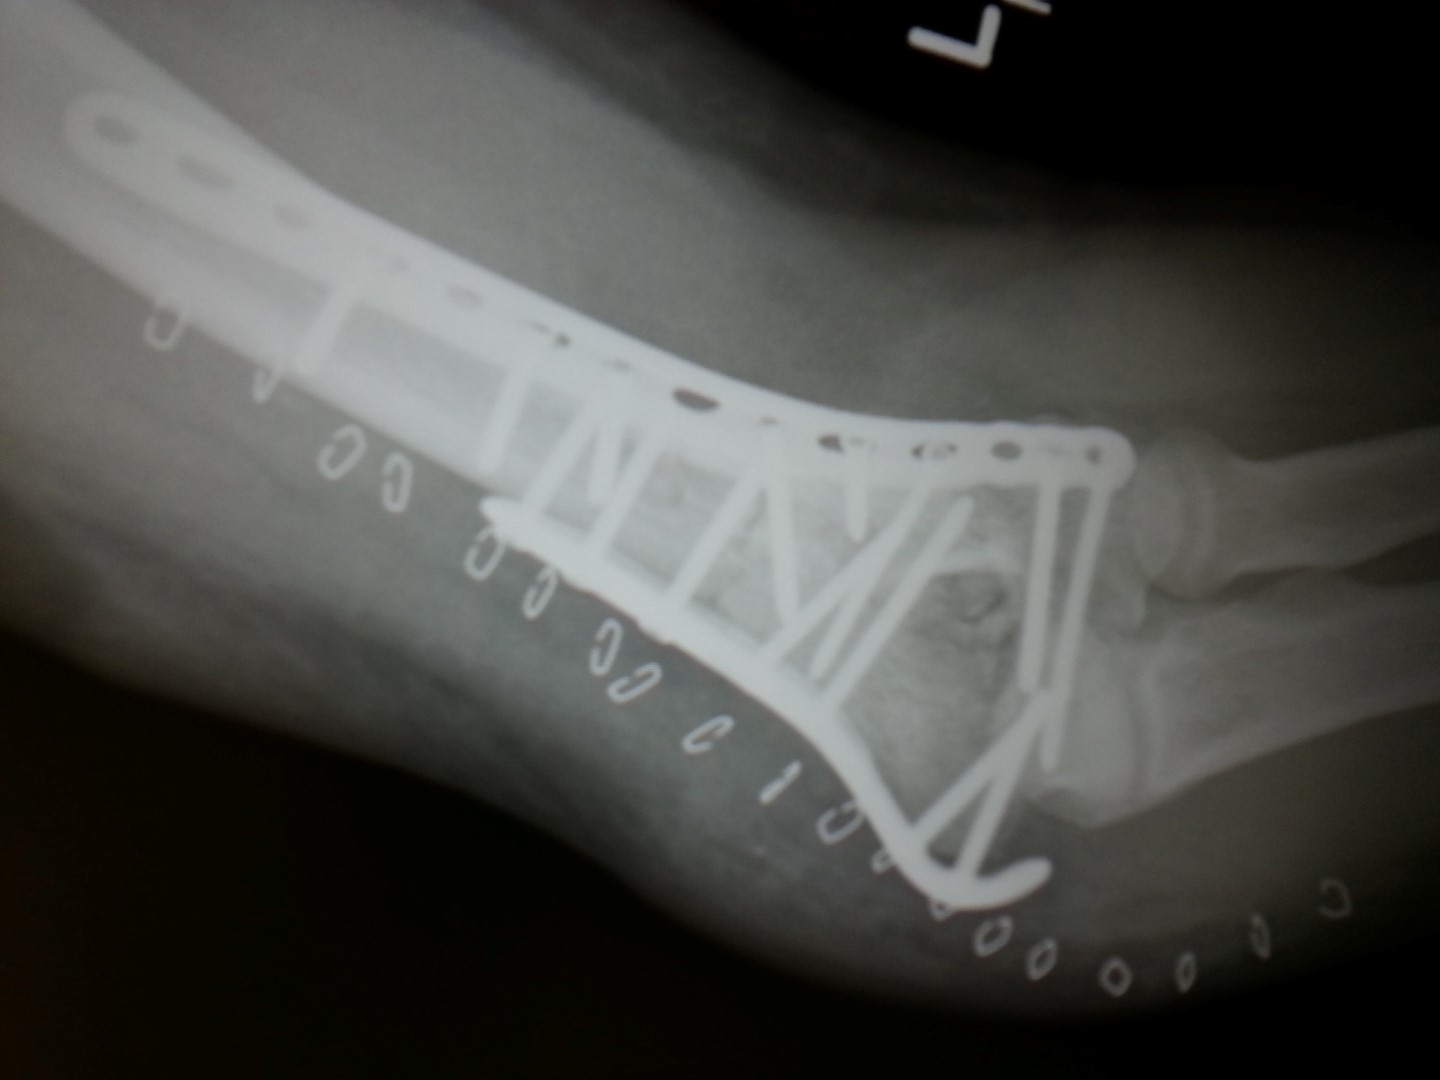

New Left Elbow